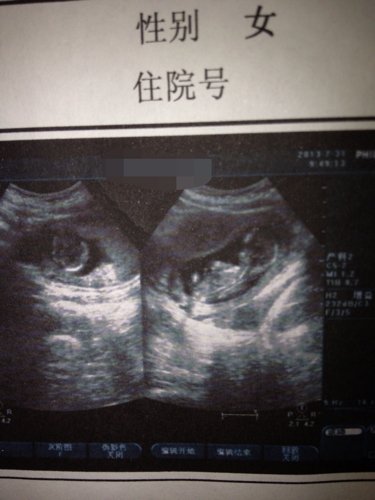

准妈妈一枚~来看看b超 能告诉我冬天我该准备粉色衣服还是蓝色衣服呢? 点击展开 匿名用户 2013-08-13 00:27 为您推荐: 其他回答 这个上面也是看不清楚的,鉴定性别也是非法的。 40529075 2013-08-13 00:29 相关问题 冬天了,准妈妈们都买什么样的衣服穿? 国外进口检测男孩女孩的、像是验孕笔一样,男孩蓝色,女孩粉色的产品、用过的宝妈告诉我 谁能告诉我!这B超能看到什么!还有那红色和蓝色是虾米